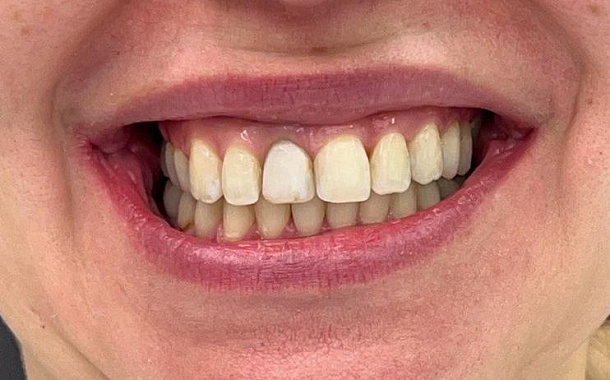

Поверхностный кариес – образуется видимый дефект в пределах эмали и могут появляться симптомы на термические раздражители: холод, кислые продукты, т.е. повышается чувствительность эмали зубов. Поверхностный кариес может развиваться в течение длительного времени без явных симптомов, но если его не лечить, то он может продвинуться в более серьезные стадии. Данную проблему возможно решить только реставрацией зуба.

Средний кариес – поражает не только эмаль зуба, но и дентин, который менее плотный и быстрее подвержен разрушению, происходит поражение находится в сердцевине зуба, где находятся кровеносные сосуды и нервы. Средний кариес проявляется болевой реакцией на горячее или холодное. Лечение среднего кариеса требует удаления пораженного участка и восстановления полости реставрационным материалом.

Глубокий кариес – распространяется на зубную пульпу, где находятся нервы и кровеносные сосуды, ведет к тотальному разрушению структур зуба с частичным вовлечением в процесс пульпы зуба. Глубокий кариес может вызвать острую боль и требует срочного лечения.

Пациент может жаловаться на боль в зубе, возникающую от механических или химических раздражителей. При осмотре доктор обнаруживает глубокую кариозную полость, в которой находится размягченный дентин. Иногда отмечаются ноющие болевые ощущения в зубе, сохраняющиеся после удаления раздражителя. Если разрушение затрагивает пульпу, для восстановления зуба потребуется лечение корневых каналов.